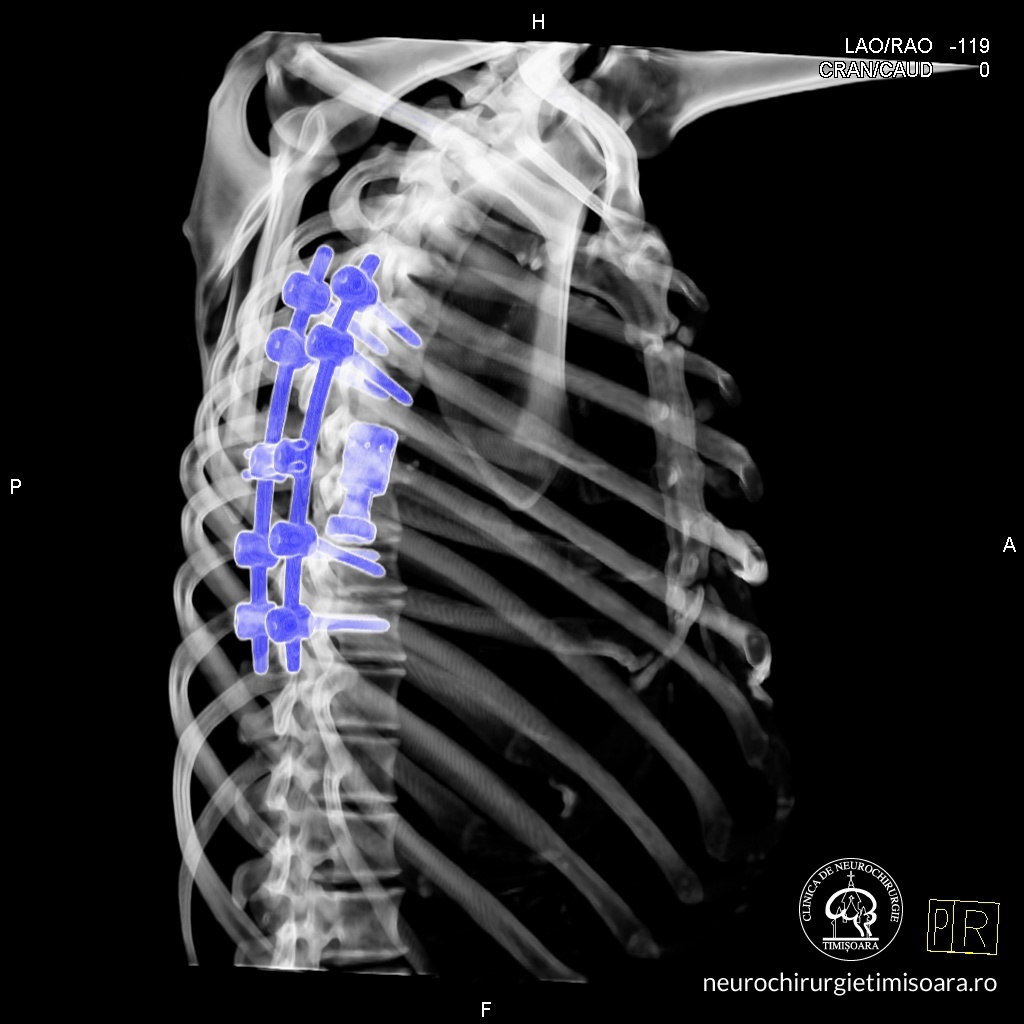

Patologia coloanei vertebrale